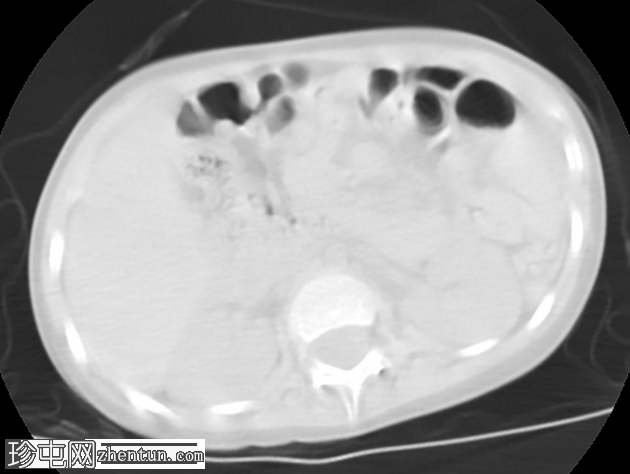

轴向

AAST IV级肝撕裂伤,伴有大面积不规则肝损伤,累及V段(轴向、冠状、矢状)。

撕裂伤区域内未见活动性造影剂外渗。

可见中等量腹腔积血。

无气腹。